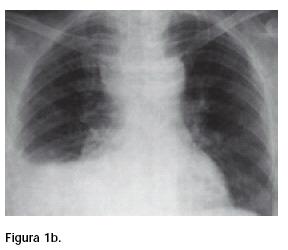

Hombre de 44 años, no diabético, no alcohólico; adoncia parcial, mala higiene bucal. Presentó infección en el alvéolo y encía de molar inferior derecho, seguida de la formación de un absceso local y de disfagia alta, hipertermia, induración, crepitación y aumento de diámetro del cuello. Al cuarto día de evolución, con anestesia general, se le realizaron dos incisiones, una submandibular y otra supraesternal, pero sus condiciones empeoraron por lo que fue trasladado a nuestro servicio. A su ingreso, drenaba pus por las heridas cervicales, estaba séptico y en estado de choque; se le tomaron radiografías de cuello (Figura 1a) y tórax (Figura 1b).

Las radiografías simples de cuello (Figura 1a) y tórax (Figura 1b) de nuestro enfermo mostraron ensanchamiento del espacio retrovisceral, desplazamiento anterior de la columna aérea de la tráquea, rectificación de la lordosis cervical, burbujas aéreas en cuello, ensanchamiento y pérdida de la nitidez de los planos blandos del mediastino con imagen redondeada paratraqueal derecha sugestiva de absceso y derrame pleural que, aunados a los datos clínicos y a su extrema gravedad, obligaron a llevarlo a cirugía con carácter de urgente.